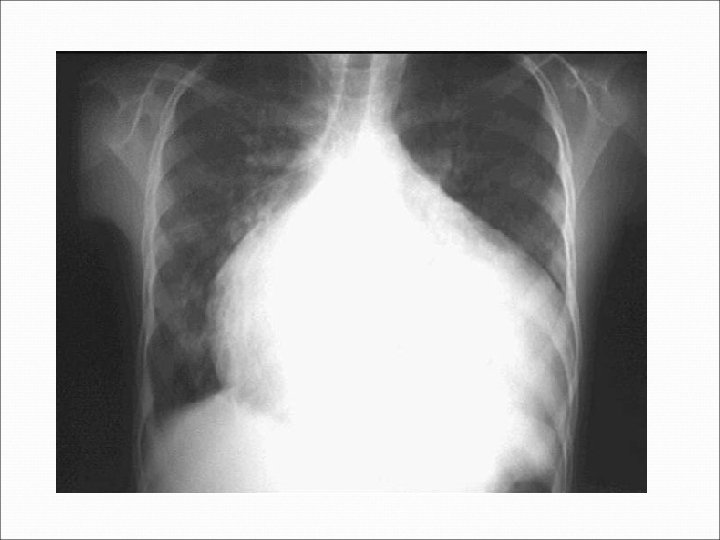

Insuficiencia Cardiaca = Signos Cardiomegalia, ritmo de galope, soplos cardiacos, ruidos cardiacos hipofóneticos. Pulsación de vasos de cara y cuello, distención venas del cuello (I. Y) Estertores crépitantes, roncus, sibilancias, derrame pleural Náusea, anorexia Ascitis, anasarca Dolor hepático, hepatomegalia, reflujo hepato yugular. Edema periférico, postural (Fovea +) Ingurgitación facial, acrocianosis, palillos de tambor (hipocratismo digital) Intolerancia al decúbito ( ortopnea) , taquipnea.

Radiografía de Tórax: Hipertensión Venocapilar Pulmonar: I. - Hilios ensanchados > 15 mm II. - Moteado fino difuso, redistribución apical III. - Líneas B de Kerley, derrames cisurales IV. - Edema alveolar (alas de mariposa)

DIAGNÓSTICO: Insuficiencia Cardiaca Izquierda con G. C. ↓ por Disfunción Sistólica secundaria a Cardiopatía Hipertensiva (Disnea, FE <50%, Hipertensión). Clase III/IV NYHA (Síntomas con poca actividad) Clasificación C: (Con daño y con síntomas) Framingham: 3 Mayores (Congestión pulmonar, S 3, Cardiomegalia) y 2 Menores (Taquicardia, Disnea de esfuerzos)